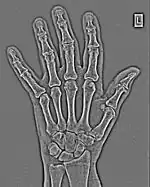

FFTs can also be calculated in two-dimensions to give results such as those in Figure 1.27. Since Fourier analysis generates results in terms of both positive and negative spatial frequencies, these can be plotted in the form of a 2D image so that the maximum frequency lies at the origin and those for the horizontal and vertical directions are shown increasing towards that origin. The modulation at different spatial frequencies is represented using a grey-scale. Low frequency bands can be seen along the horizontal axis in the figure, for example, representing the horizontal periodicity of image data from the fingers, while finer bands along the y-dimension are indicative of a periodicity of image data from the various metacarpophalangeal joints. Higher frequency features can also be seen running diagonally in this 2D-FFT, representative of the trabecular structure of the bones, for example.

The essence of this approach is that it can be used to produce a range of image processing effects by enhancing and/or suppressing features in the 2D-FFT and then converting the result back into the spatial domain using the IFT, as illustrated in Figure 1.28. Such image manipulations are considered in more detail in a later chapter. Note that the form of image processing demonstrated in the figure is for purely illustrative purposes and bears no direct medical significance.